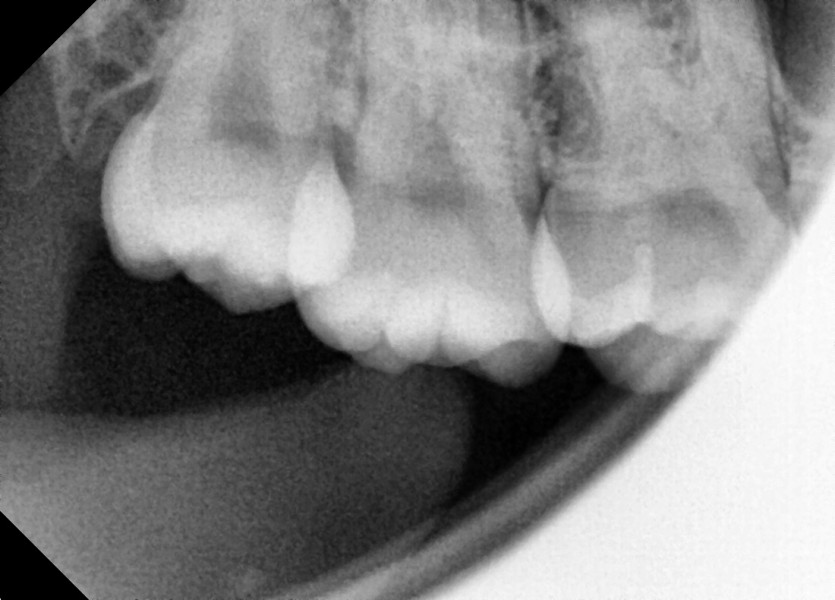

#18,48 사랑니 발치

구강외과 전문의가 당일 발치 했씁니다.